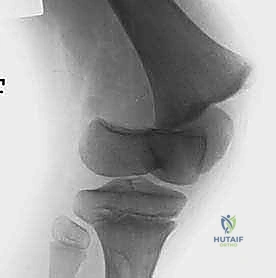

2. التصوير بالأشعة السينية (X-rays)

الخطوة الأساسية والأولى. يتم أخذ صور بأوضاع متعددة (أمامي خلفي، وجانبي، ومائل). في بعض الأحيان، قد يبدو الكسر غير مرئي بوضوح إذا لم تتحرك العظام من مكانها (Nondisplaced)، وهنا تبرز خبرة الطبيب في قراءة العلامات غير المباشرة مثل اتساع خط صفيحة النمو أو تورم الأنسجة العميقة.

تصنيف كسور صفيحة النمو: نظام سالتر-هاريس (Salter-Harris)

لغة التخاطب بين أطباء جراحة العظام حول العالم تعتمد على نظام تصنيف "سالتر-هاريس". هذا التصنيف لا يصف شكل الكسر فحسب، بل يرشد الأستاذ الدكتور محمد هطيف في تحديد استراتيجية العلاج الدقيقة وتوقع النتائج المستقبلية لنمو الطفل.

النوع الثالث (Type III) والنوع الرابع (Type IV): الكسور داخل المفصل

هذه الكسور أكثر خطورة لأنها تخترق سطح المفصل وتدمر طبقات الخلايا الجذعية في صفيحة النمو.

* النوع الثالث (III): يبدأ الكسر من داخل المفصل، يمر عبر المشاشة (Epiphysis)، ثم يمتد أفقياً عبر صفيحة النمو.

* النوع الرابع (IV): كسر عمودي خطير. يمتد من السطح المفصلي للركبة، صعوداً عبر المشاشة، مخترقاً صفيحة النمو بالكامل، ومستمراً إلى داخل عظم الكردوس.

* التوقعات: تحمل هذه الإصابات داخل المفصل خطراً عالياً جداً لاضطرابات النمو، وتكوين جسور عظمية غير طبيعية (Physeal Bars)، وعدم تطابق الأسطح المفصلية (مما يؤدي لالتهاب المفاصل المبكر). تستدعي هذه الحالات تدخلاً جراحياً دقيقاً لإعادة العظم إلى وضعه التشريحي بدقة متناهية.